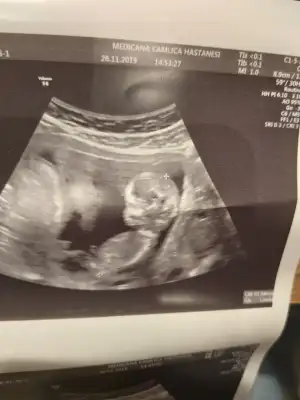

Erkek diyorum kaç haftalık usg

erkek gibi başka usg var kaç haftalık